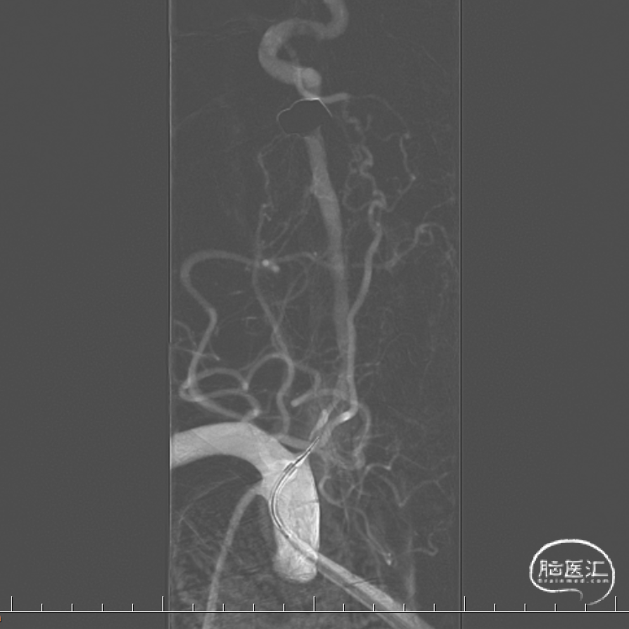

沿微导丝先后送入4.0*16mm、4.0*12mm Maurora®药物洗脱支架共2枚于椎动脉狭窄段,定位准确后以分别以12、14atm释放。

复查DSA显示右侧椎动脉残余狭窄大于40%,沿微导丝送入4.5*15mm 优游球囊于椎动脉狭窄段后扩张,回撤球囊。

复查DSA显示右侧椎动脉残余狭窄小于30%,血流通畅,术中无新发部位栓塞;拔出鞘管,股动脉缝合器行血管缝合,止血成功,绷带加压,安返病房,行血压、脉搏监测,常规抗血小板治疗。